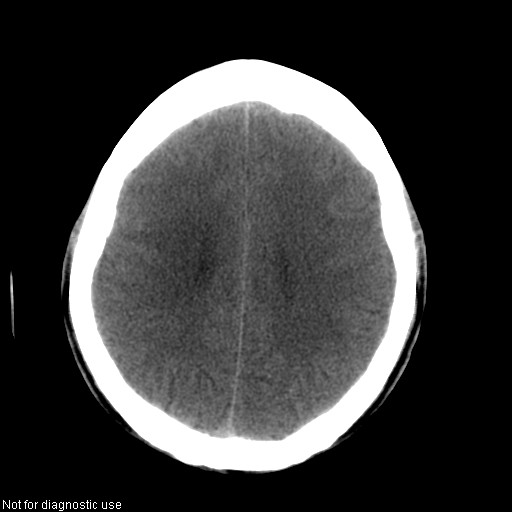

以下是引用hhcckk在2008-1-26 16:03:00的发言:[br]考虑病毒感染可能性大[br]1、病人发病时间短,1周,转移病灶时间长[br]2、楼主虽然没有告诉我们年龄,但从颅内情况来看,病人年纪不会很大,脑池,脑沟不是很明显,当然,可能有脑肿胀的原因,转移灶病人年纪一般较大[br]3、从病灶特点来看,转移多发生在灰白质交界区,多有指状水肿,占位效应明显,此病人呈对称性发布,发生在脑实质深部,与转移有所区别[br]4、病人经抗炎,止咳效果不好,可能是病毒感染,抗生素治疗效果不好[br]5、建议楼主1、增强 2、有呼吸系统的症状何不拍个胸片